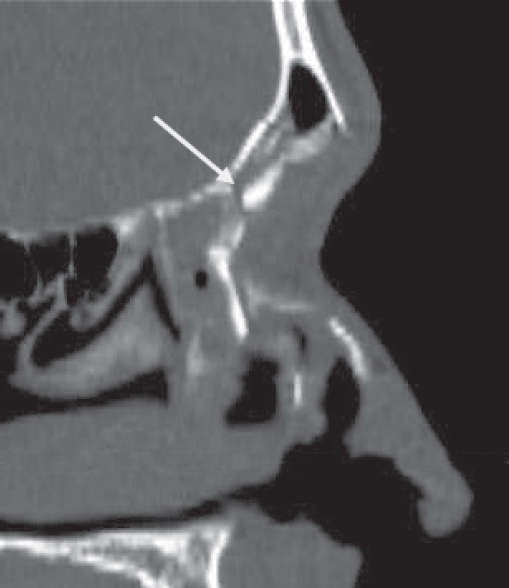

Historically, plain sinus X-rays were used to evaluate facial fractures. Thin cut (1–1.5 mm) axial computed tomography (CT) scans are now the gold standard for diagnosis of frontal sinus fractures. These images are readily reformatted into coronal, sagittal, and threedimensional (3D) reconstructions to improve the diagnostic accuracy. Axial cuts provide excellent information about the anterior and posterior table as well as pneumocephalus ( Fig. 63.5 ). Coronal reconstructions demonstrate the frontal sinus floor, orbital roof, and frontal recess ( Fig. 63.6 ). Sagittal views can assist with evaluation of frontal recess and skull base injuries ( Fig. 63.7 ). Threedimensional reconstructions can be very helpful in delineating the location of bone fragments and reducing the need for excessive dissection intraoperatively ( Fig. 63.8 ). Access to the PACS ( p icture a rchiving and c ommunication s ystem) or some type of presurgical planning software allows the surgeon to manipulate the reconstructions in space, gaining a greater understanding of depth and spatial relationships of the injury ( Video 63.1).